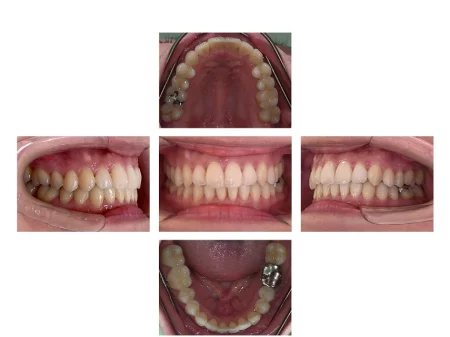

歯並びがきれいに整い、見た目と噛み合わせが改善しました。

患者様も「きれいになって嬉しい」と非常にご満足されており、笑顔も増えているご様子です。

現在は、後戻り防止装置の「リテーナー」を使用しながら、きれいな状態を維持するために定期的にご通院いただいています。

- 治療期間の目安2年3ヵ月

治療費総額の目安705,000円 - 【内訳】

- インビザラインフル 590,000円

- 検査代 30,000円

- 経過管理料 5,000円×11回

- 保定装置代 30,000円